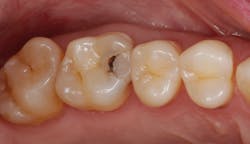

While performing esthetic dentistry, our bonding materials must work as promised to achieve long-term success.2 When manufacturers report bond strengths in the clinical arena, studies are conducted with the rubber dam in place (figures 1 and 2). When etched surfaces are exposed to the oral environment, including expired air while using typical isolation devices, the surfaces are challenged by moisture from numerous sources, causing the adhesive chemistry to be altered. Hence, to achieve the best bond strengths, a well-sealed barrier will help our results, often dramatically.